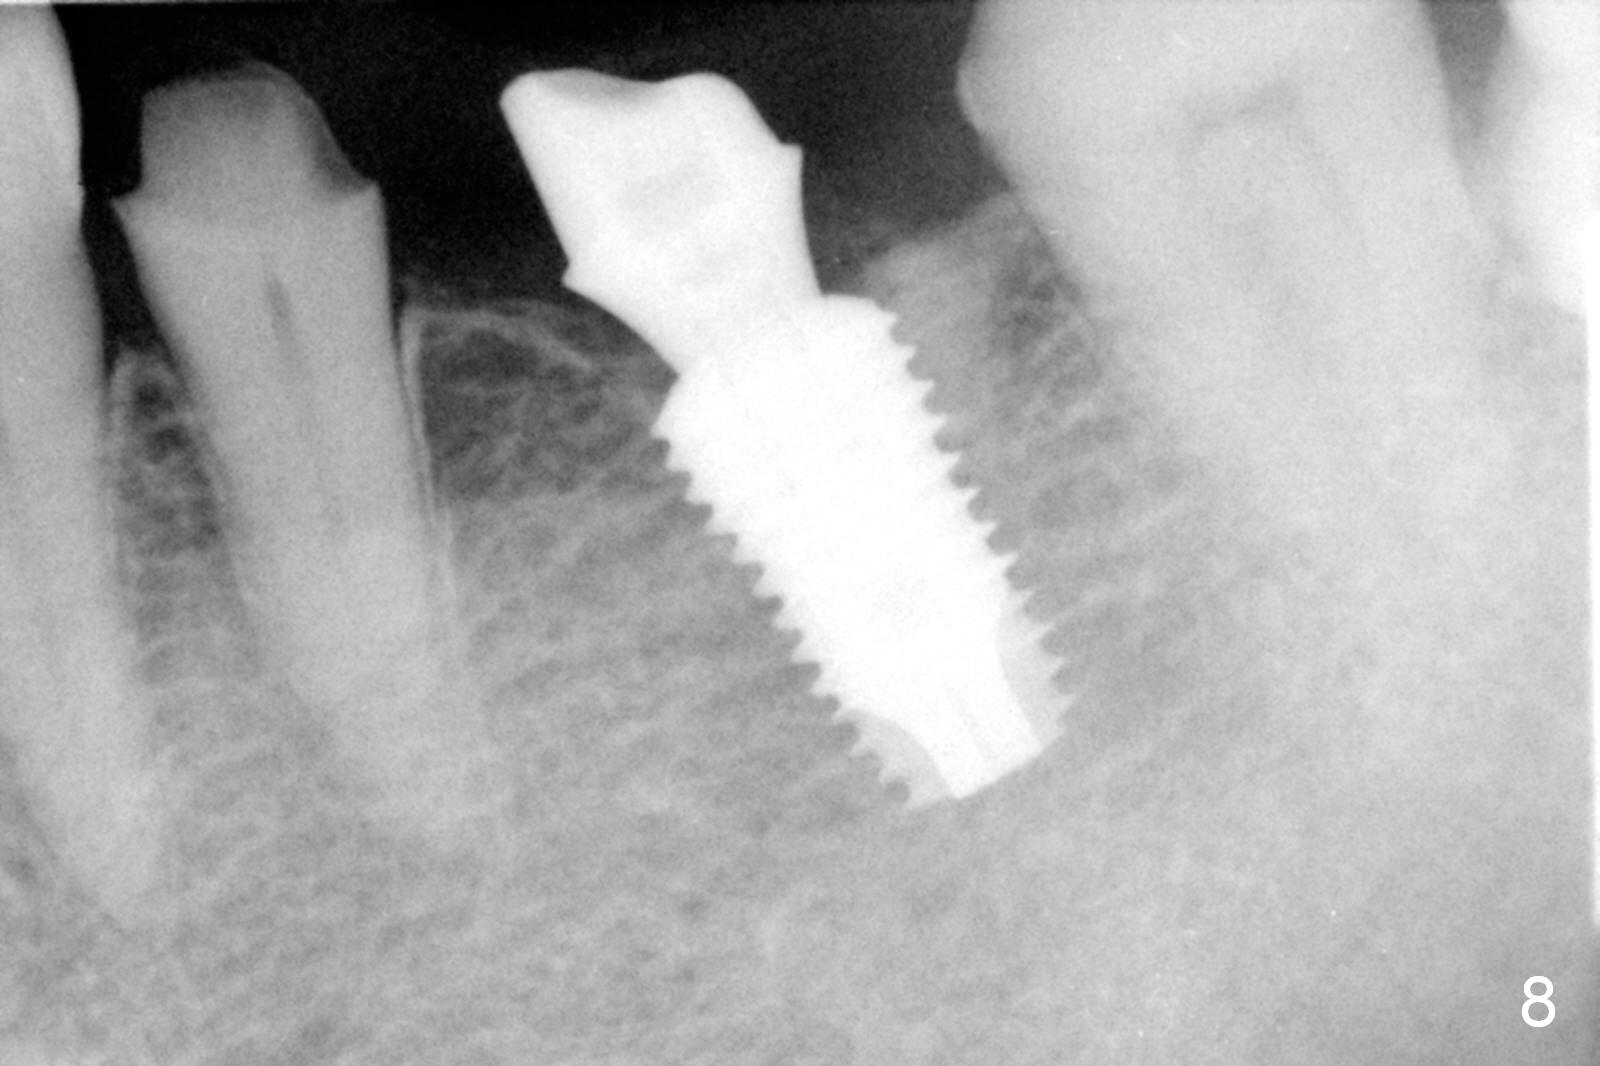

The patient returns for restoration 13 months postop with implant osteointegration (Fig.8) and formation of gingival cuff around the implant/abutment (Fig.9 *). In fact the immediate provisional seems to help mastication to certain degree (Fig.10). Probably it has resisted supraeruption of the opposing dentition. Impression is taken without torque of abutment screw. He smokes again.

The access is mesial at #19 (Fig.11 v). After cementation, the abutment screw is torqued through the access, which is then closed with flowable composite (Fig.12 *).